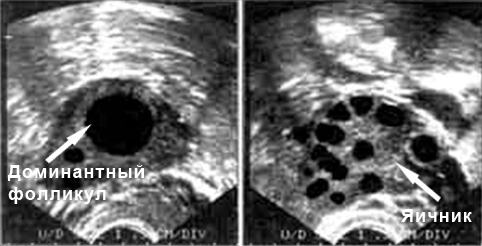

На текущем УЗИ будет видно доминантный фолликул, диаметр которого варьируется от 17 до 30 мм. Непосредственно перед овуляцией в фолликуле можно заметить характерный бугорок, где происходит созревание яйцеклетки. В этот период слизистая оболочка матки также утолщается.